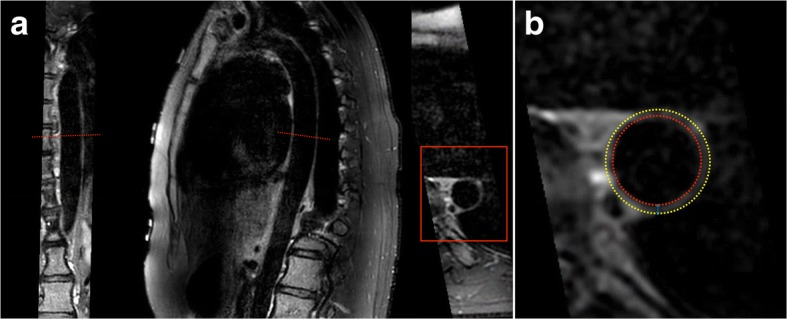

Subsequently, descending thoracic aortic wall geometry was quantified using a customized software program specifically developed for measuring geometric dimensions of arterial walls (Vessel Mass, release 5.1, Laboratory for Clinical and Experimental Image processing (LKEB), The Netherlands) [10]. The used quantification methods have previously shown to have an excellent reproducibility for aortic wall geometry assessment (intraclass correlation coefficient (ICC): 0.76–0.99) [7]. An in depth description of image analysis can be found elsewhere [7, 8]. In short, aortic wall geometry was assessed using the images between the origin of the descending thoracic aorta and the origin of the celiac trunk. A sample of the first 50 participants showed that, on average, in each participant ~ 22 cm (cm) of aorta was analysed (mean: 21.9 cm, [SD: 1.8], median: 22.0 cm [Q1: 21.0, Q3: 23.0]). Per cm of aorta, 1 image was assessed for aortic wall geometry via manual tracing of the aortic wall boundaries by an experienced researcher (AE, 3 years experience in aortic wall geometry assessment). On average, aortic wall geometry was assessed in 22 images per participant. Based on the traced contours, the software Vessel Mass automatically computed the mean aortic wall area and thickness in each participant according to a previously described method by summing the mean aortic wall area (cm2) and thickness (mm) for all slices in that participant and divide it by the number of quantified slices in that participant [7, 10]. Fig. 1 provides examples of descending thoracic aorta CMR-images as well as a schematic representation of aortic wall geometry assessment.

Fig. 1.

Example of measurement and quantification of aortic wall geometry. Coronal reconstruction (a, left), sagittal double oblique source image (a, middle) and transverse double oblique reconstruction (a, right) of the thoracic aortic vessel wall obtained with the 3D-T1-BB-VISTA acquisition in a 32 year female. In panel b aortic wall thickness measurements are illustrated. Vessel wall thickness is calculated by the area of the wall between the red inner red and yellow outer vessel wall contours. Wall thickness is calculated by the distance between the contours (blue arrow). The software VesselMass automatically subdivides the aortic wall into 4 segments. In each segment, 25 aortic wall geometry measurements are performed